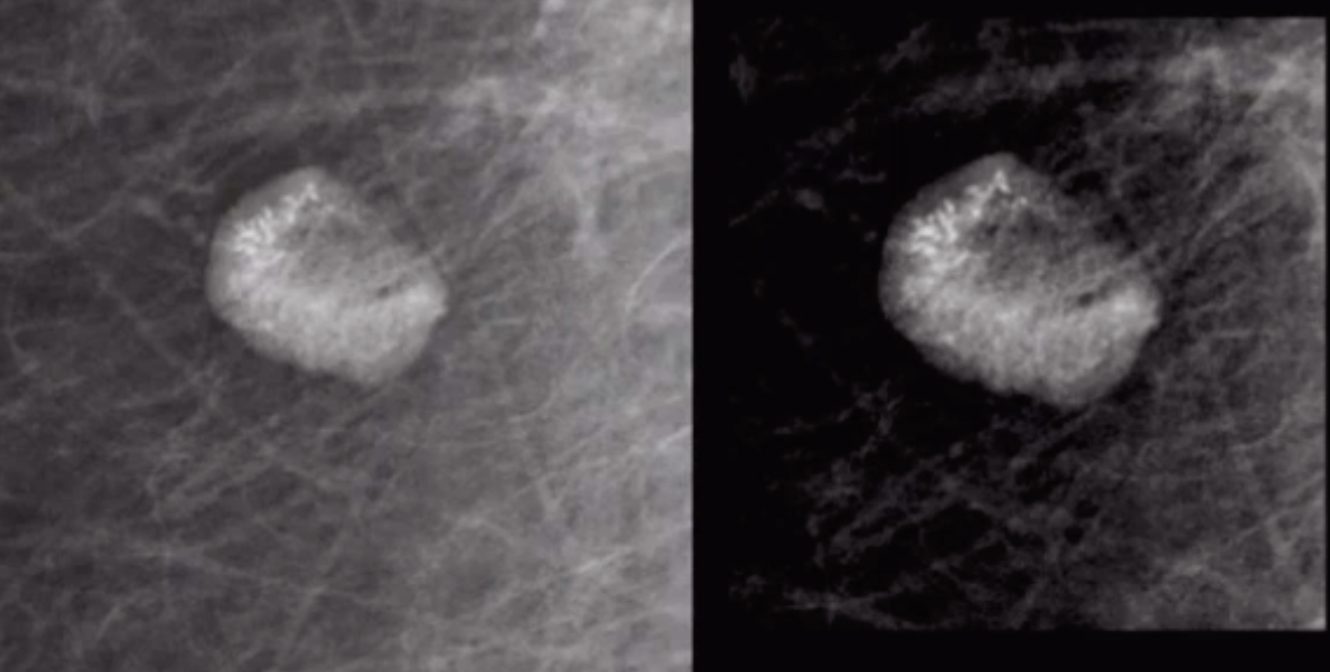

Phyllodes tumor

• Middle to older women

• Basically same appearance as fibroadenoma but in older patient (50+)

• Homogenously hypoechoic , well circumscribed mass on US

• Not benign

• Need wide margin resection